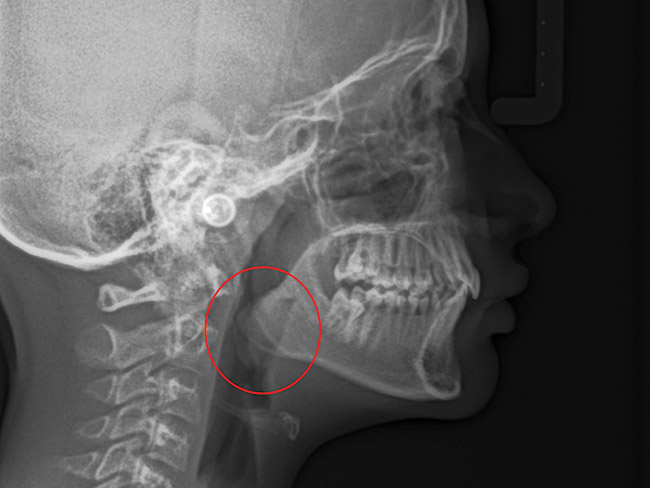

(13.) Seven-year-old brachyfacial child with high body mass index (Case courtesy of James Awbrey, DMD).

Figure 13

(14.) Angle Class III occlusion with constricted maxilla.

Figure 14

(15.) Cephalometric evaluation demonstrates significant tonsillar blockage of the airway and bimaxillary retursion.

Figure 15